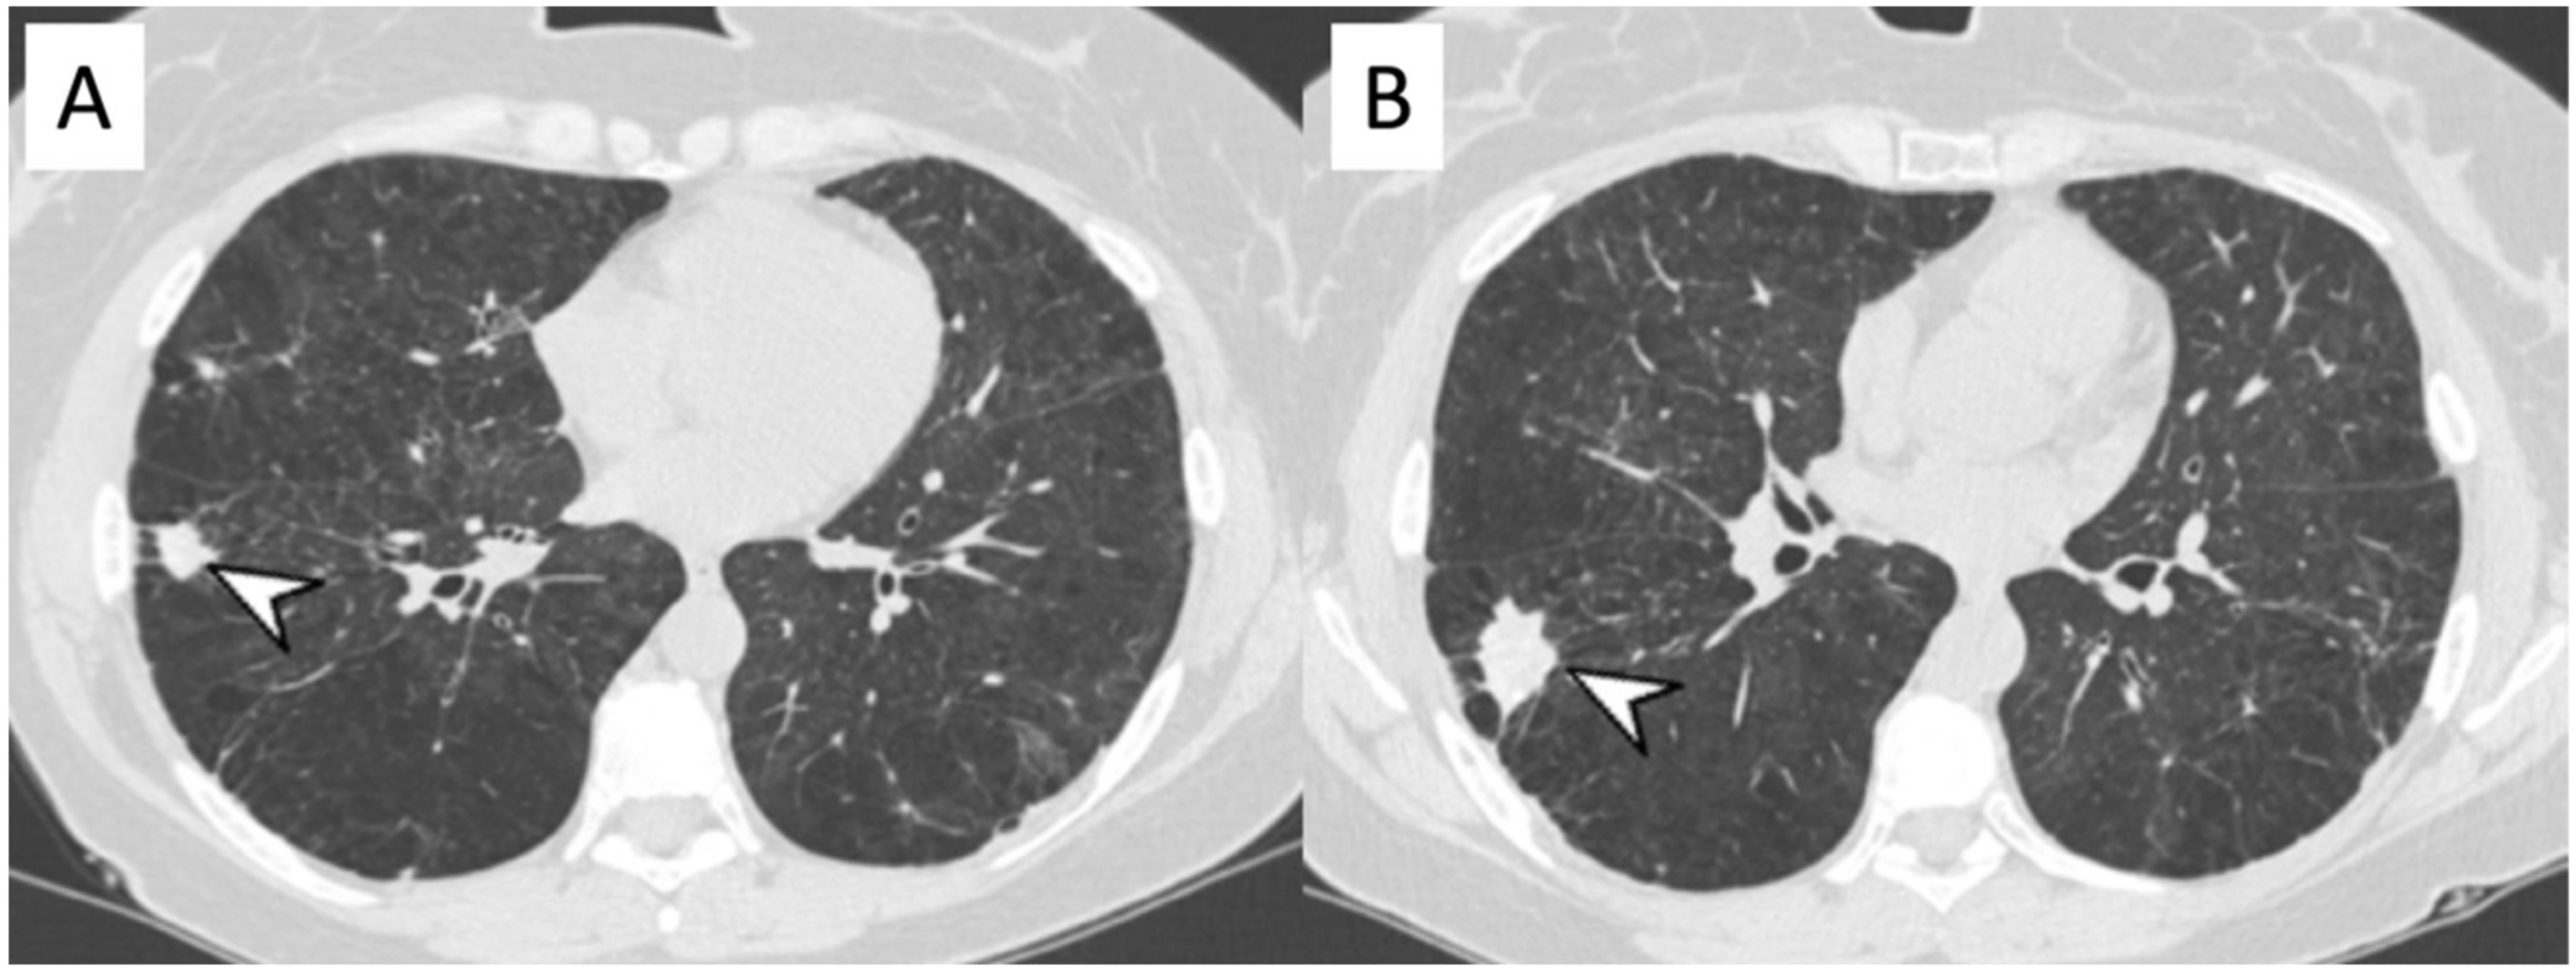

2.4. Granulomatosis with Polyangiitis (GPA-Wegener’s Disease)

| GPA | Solid nodules, GGOs due to hemorrhagic alveolitis (common); halo sign, crazy paving (less common) |